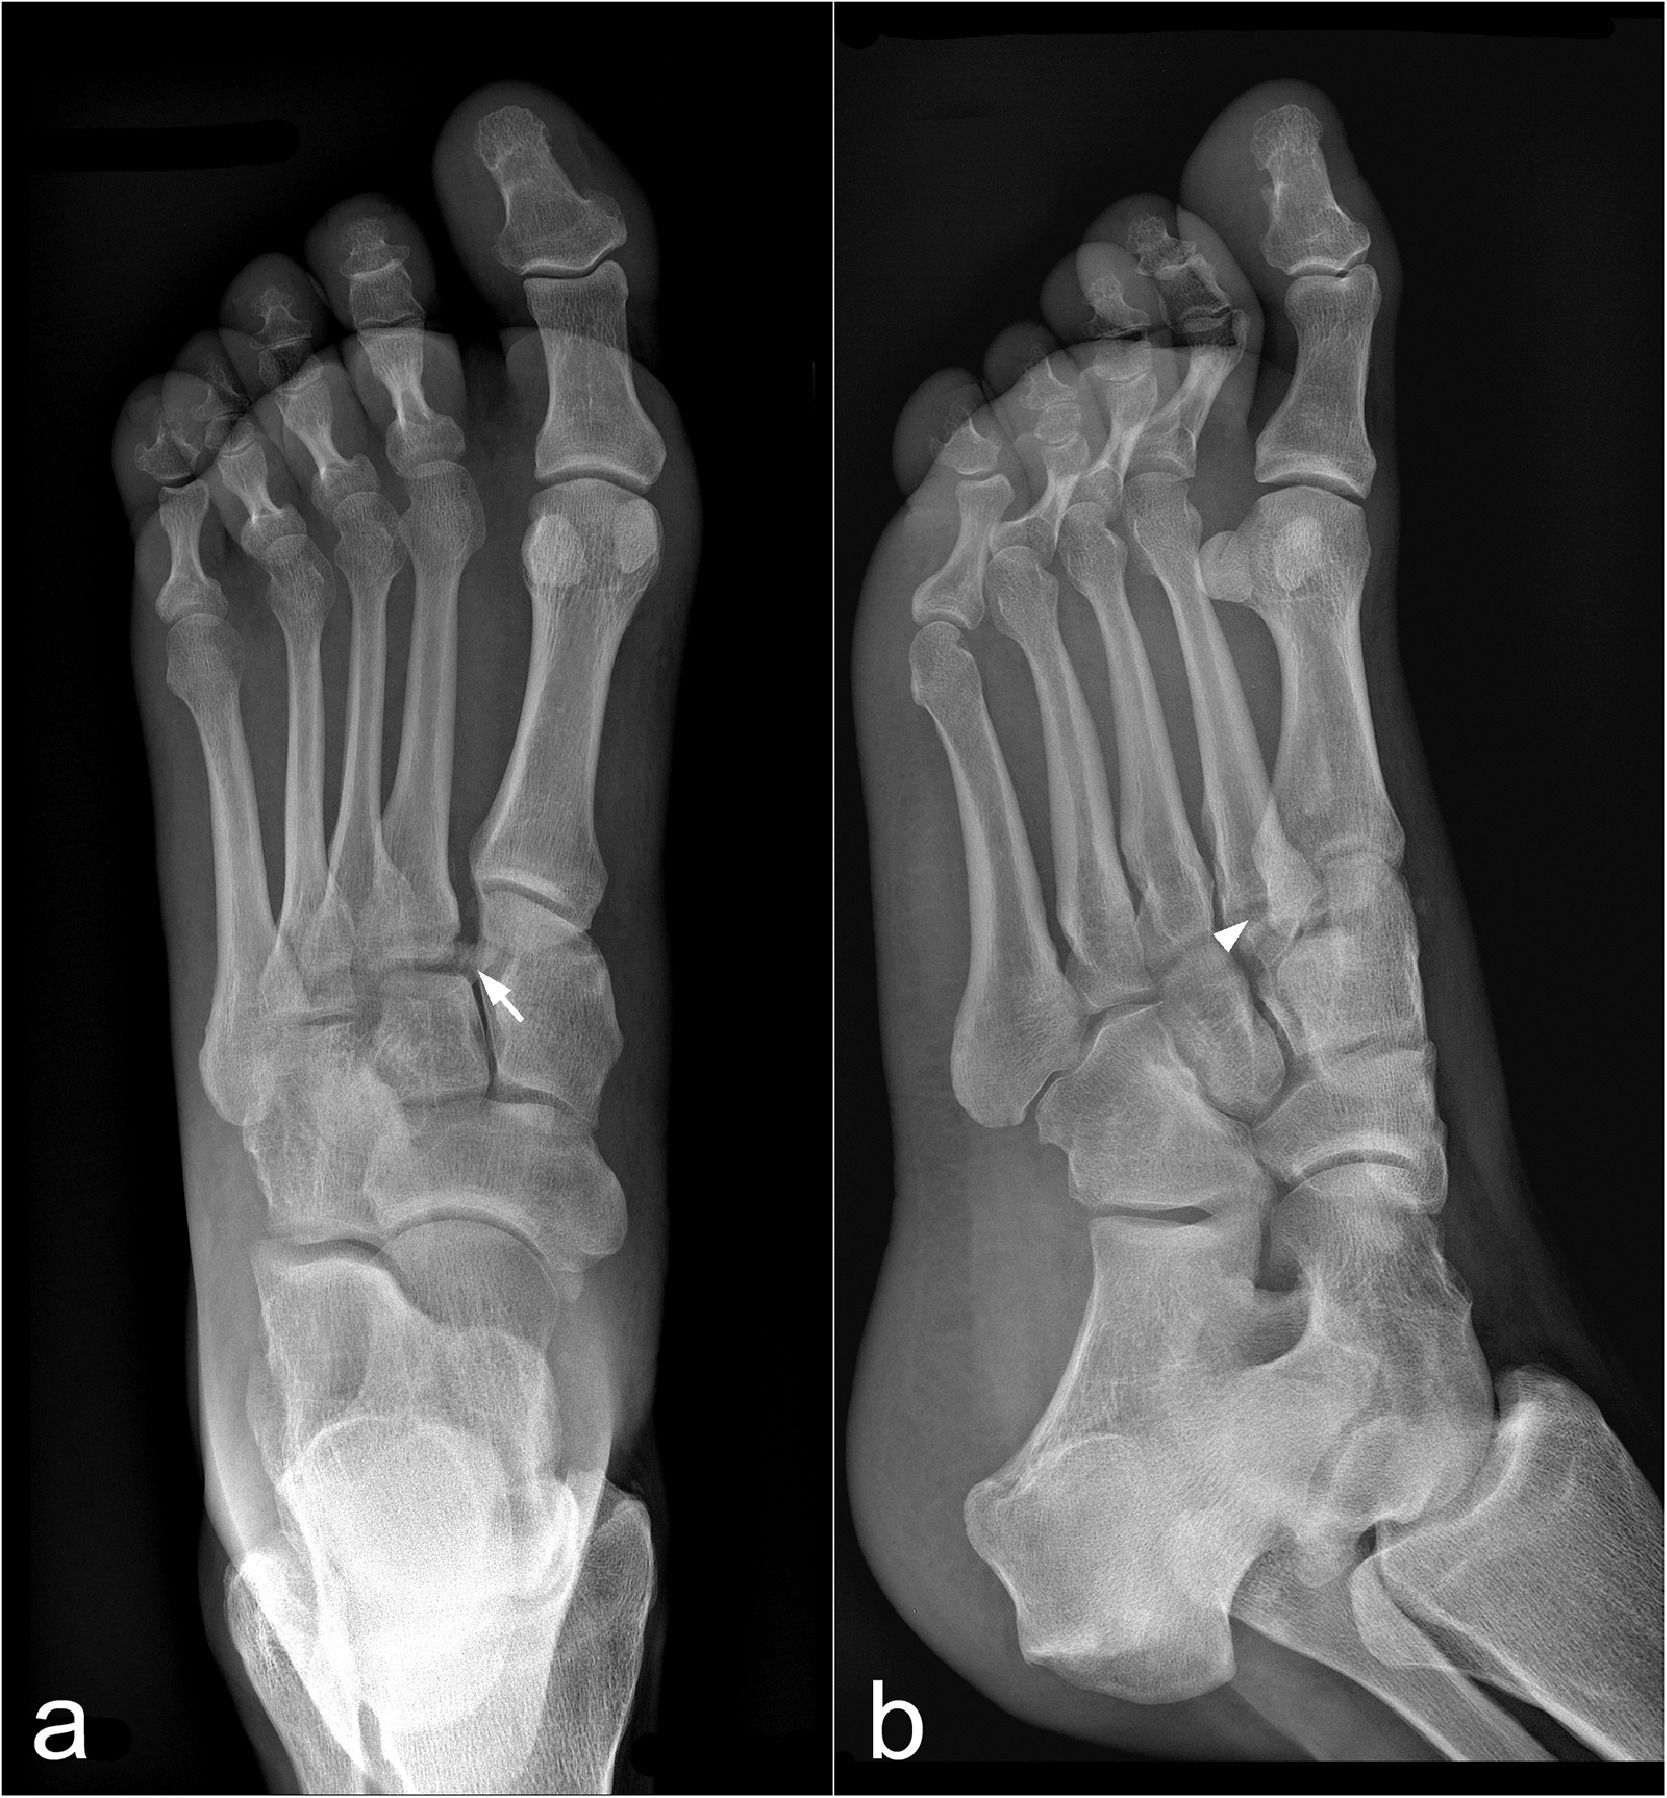

The authors of a new meta-analysis found no significant differences between clinicians and artificial intelligence in diagnosing fractures but conceded that slightly over half of the studies assessed had a high risk of potential bias.

What is your diagnosis?